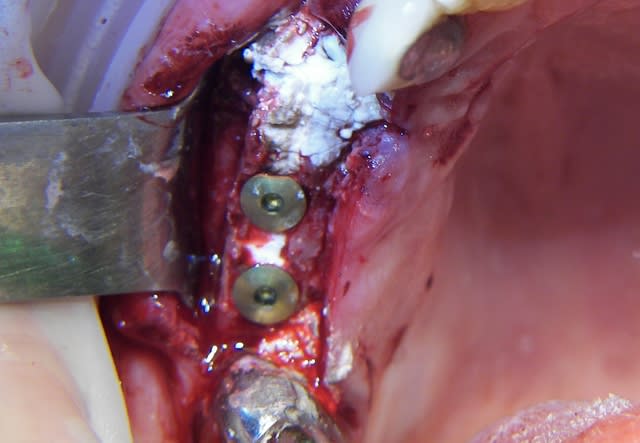

Je crois que je tenterais une "simple" expansion si possible avec des ostéotomes curvilignes de Tatum pour 22 + implant éventuellement VitalOs

Si tout se passe bien tu vas rétablir un joli bombé vestibulaire et tu pourras gérer ensuite la centrale.

Ce n'est pas le même cas mais ça montre ce que donne une expansion faite en 91 (14) malgré une surveillance très épisodique

J'ai aussi entendu beaucoup de chose sur le Vitalos mais je trouvais le concept sympa et je me refuse à utiliser ce qui n'est pas d'origine synthetique donc j'ai voulu essayer et tres honnetement si tu respecte le protocole c'est un produit qui me semble plus que sympa.

d'autant plus que le SAV est vraiment parfait

pour les photos il s'agit d'un bone splitting mais ce ne sont que des photos....... pas une preuve irrefutable